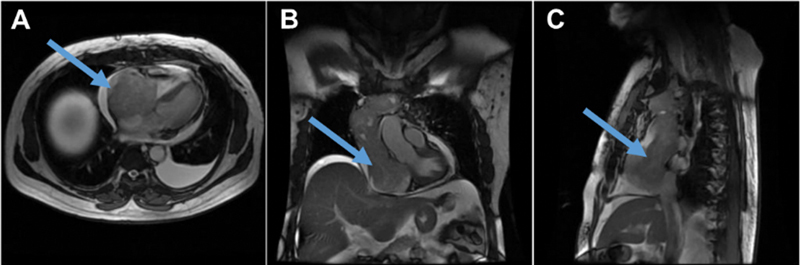

A unique case of papillary carcinoma of the thyroid with an extensive tumor thrombus extending into the right ventricle is presented. The patient was a known case of solid variant of papillary carcinoma of thyroid, post three cycles of radioiodine therapy, had reported for a diagnostic 131 I-NaI scintigraphy as a part of the workup for planning the next 131 I therapy. Clinically, the patient was asymptomatic. 131 I-NaI scintigraphy showed an arcuate pattern concentration of tracer in the upper mediastinum, which descended up to the lower mediastinum. A 131 I-NaI single photon emission computed tomography/computed tomography (SPECT/CT) showed a tracer avid tumor with an extensive tumor thrombus extending from the left brachiocephalic vein to the right ventricle. 18 F-fluorodeoxyglucose positron emission tomography/computed tomography ( 18 F-FDG-PET/CT) and magnetic resonance imaging (MRI) demonstrated similar findings. The patient was decided to be managed with tyrosine kinase inhibitors as surgical intervention was not deemed possible due to the involvement of major vessels and the high risk of bleeding.